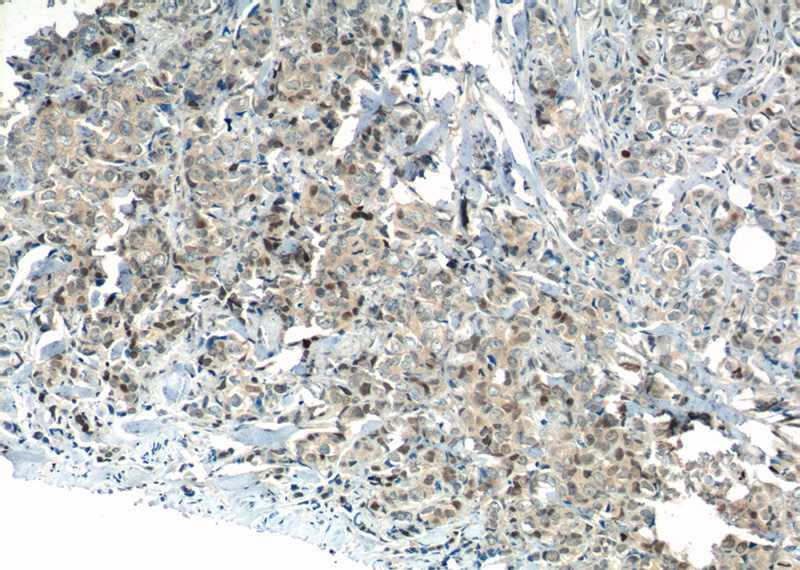

Immunohistochemistry of paraffin-embedded human breast cancer tissue slide using Catalog No:112041(KI67 Antibody) at dilution of 1:400 (under 10x lens). heat mediated antigen retrieved with Sodium Citrate buffer (pH6).